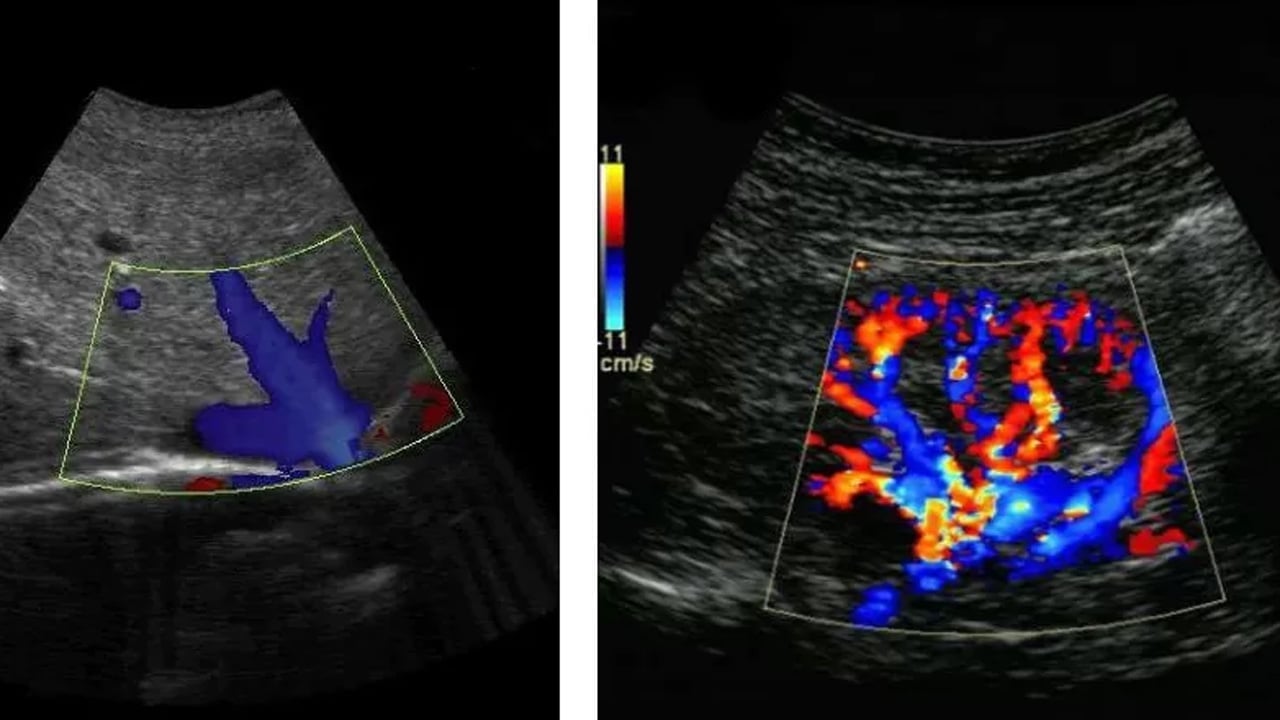

Örneğin karaciğerin diyaframa yakın bölgelerinde yer alan bir kitle, hastada omuz ya da sağ üst karın bölgesinde ağrı hissi oluşturabilir. Bu nedenle her hastada belirtiler farklı şekillerde ortaya çıkabilir. Hafife almayın, önemli ipuçları olabilir Prof. Dr. Koray Topgül, karın içi kitlelerin verdiği erken sinyallerin çoğu zaman göz ardı edildiğini kaydederek, "En sık karşılaşılan belirti ağrıdır. Bunun yanında geçmeyen ya da giderek artan şişkinlik, daha önce yaşanmayan tarzda karın ağrıları ve tekrarlayan rahatsızlık hissi önemli ipuçlarıdır. Bu şikâyetler genellikle çok şiddetli olmadığı için hastalar tarafından önemsenmez. Ancak bu durum tanının gecikmesine yol açabilir" ifadelerini kullandı. Karın içi kitlelerin değerlendirilmesinde en kritik rolü radyolojik yöntemlerin üstlendiğini aktaran Prof. Dr. Koray Topgül, şöyle devam etti: "Fizik muayene ve hasta öyküsü önemli olmakla birlikte, ultrason, bilgisayarlı tomografi ve manyetik rezonans gibi görüntüleme yöntemleri tanıda belirleyici rol oynar.